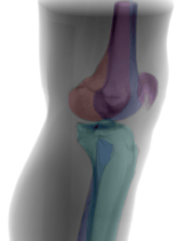

(1) Field-of-view cropping: Prevents superposition of the other laterality in the projection domain. (2) Laterality alignment: Prohibits ambiguities during pose estimation. (3) Definition of 3D reference planes: Two independent raters defined the 3D reference planes in the CT volumes utilizing a DRR preview integrated into the open-source Medical Imaging Toolkit [21] with interactive plane positioning. They serve as ground truth pose reference during simulation. (4) 3D automatic bone segmentation: To compute automatic 3D segmentations, a 3D nnU-Net [9] is trained on a subset of 10 manually annotated CTs for the task of multilabel bone segmentation, segmenting the femur, tibia, fibula, and patella. (5) Suitable segmentation representation: The two femur condyles are not distinguishable in the shape-based representation, however, this is relevant for optimal lateral view recognition. Annotating the condyles as line features would result in an increased manual labeling effort in the projection domain. Alternatively, we propose to incorporate this information in the segmentation by separating the femur annotation symmetrically along the femoral shaft (Fig. 2(a)). This results in one additional segmentation label for the lateral standard to recognize condyles’ congruence and derive the directional pose offset. (6) DRR and mask simulation: DRRs are simulated for varying angulations of orbital and angular rotation around the defined reference standard. The DeepDRR simulation framework was extended to allow the forward projection of corresponding masks (Fig 2(b)).

(2) Shape-based pose regression: Following surgical characteristics for recognizing correct standard views of the knee, a view-independent shape-based pose regression framework was developed. The architecture is based on a 2D U-Net [12] with two view-specific segmentation heads, because the segmentation labels differ for both views. The extracted shape features are used as input for the pose regression network that outputs the necessary C-arm pose update (, , , ) to acquire the desired standard view [11].

Fig. 7 shows the importance of individual segmented bone classes on the overall positioning performance evaluated on the test DRRs (3528 DRRs). The fibula has very little influence on the positioning for both views. The patella is only important for the a.-p. view, while tibia and femur are relevant for both views. The condyle assignment for the lateral view determines the rotation direction for the orbital and angular rotation (, ). Inverting the assignment of left and right femur condyle results in a sign flip in , .